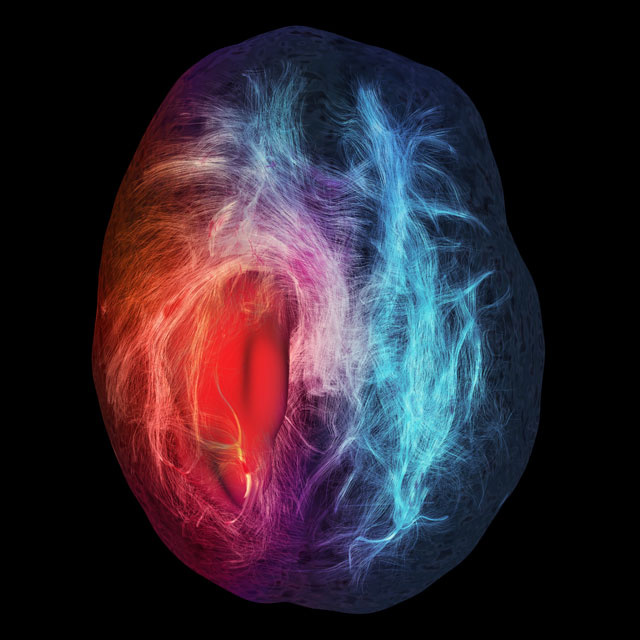

Mención de honor en ilustración, esta imagen muestra un tumor cerebral (en rojo a la izquierda). Las fibras rojas representan peligro, si se tocan durante una operación pueden dañar funciones cerebrales. Las fibras en azul muestras conexiones neuronales lejos del tumor. La imagen sirve para orientar a los cirujanos en estas delicadas intervenciones. Fue creada por ordenador por la estudiante de ciencias de la computación Maxime Chamberland.